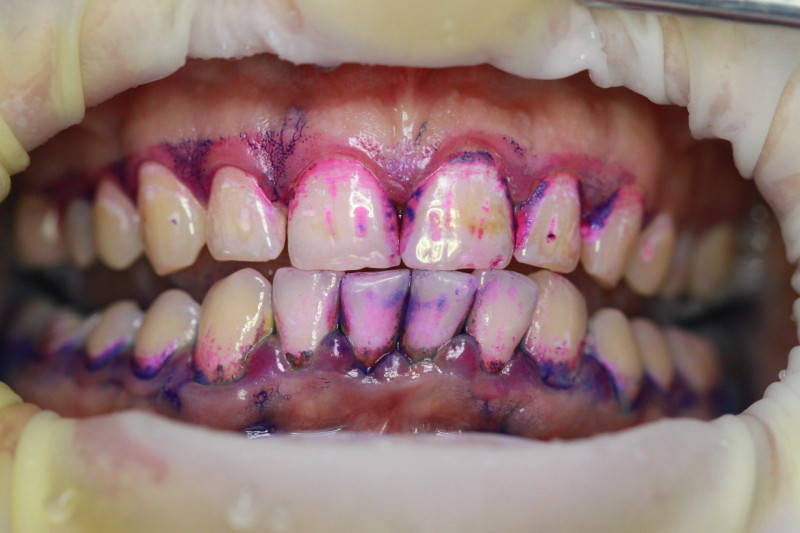

Index Dual работает по принципу селективного окрашивания: свежий налёт (до 24 часов) становится розовым, а зрелый кариесогенный налёт (более 24 часов) — синим.

Двухтоновая формула Дифференцирует свежую и старую биопленку

Высокая контрастность Хорошо видно даже в пришейной зоне

• Чёткая контрастность: Синий цвет настолько интенсивный, что его невозможно спутать с естественной пигментацией или гиперемией дёсен.

• Скорость реакции: Окрашивание происходит мгновенно после контакта с биоплёнкой.

Используйте микробраш или ватную палочку. Нанесите на все поверхности зубов, подождите 10–20 секунд и попросите пациента прополоскать рот водой.